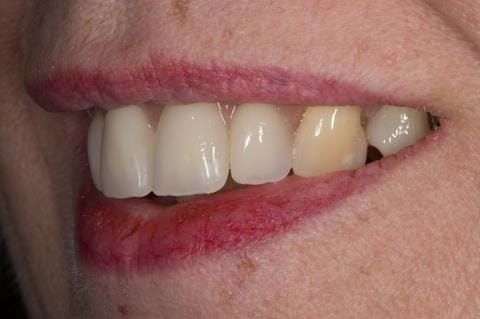

- High smile line showing gum above gingival zeniths of upper front teeth when smiling. Aesthetic failure of the upper four incisors with inflammation of the gingivae and mis-match of the gingival zenith levels.

- Extract the upper 2-2 teeth and replace with an interim acrylic based partial denture. Reline the interim denture over 9 - 12 months, replacing with a definitive cobalt chromium based partial denture. The definitive denture would ideally be designed as an occlusal protective splint to reduce the the potential for mechanical wear and breakages of the moderately/heavily restored maxillary dentition. In addition, should further upper teeth require extraction they could be added on to the denture cobalt chromium framework - therefore a new prosthesis would not be required as future teeth are lost. This option would produce an excellent aesthetic outcome. This is the option the patient chose to have.

Following consultation and second discussion appointment the patient chose to have option 3 namely, a maxillary cobalt chromium based partial denture/protective occlusal splint. The clinical situation and treatment process is shown in detail below with photographs. The patient was successfully rehabilitated with this and her quality of life considerably improved. The clinical work was provided by Finlay and the technical work by Rowan.